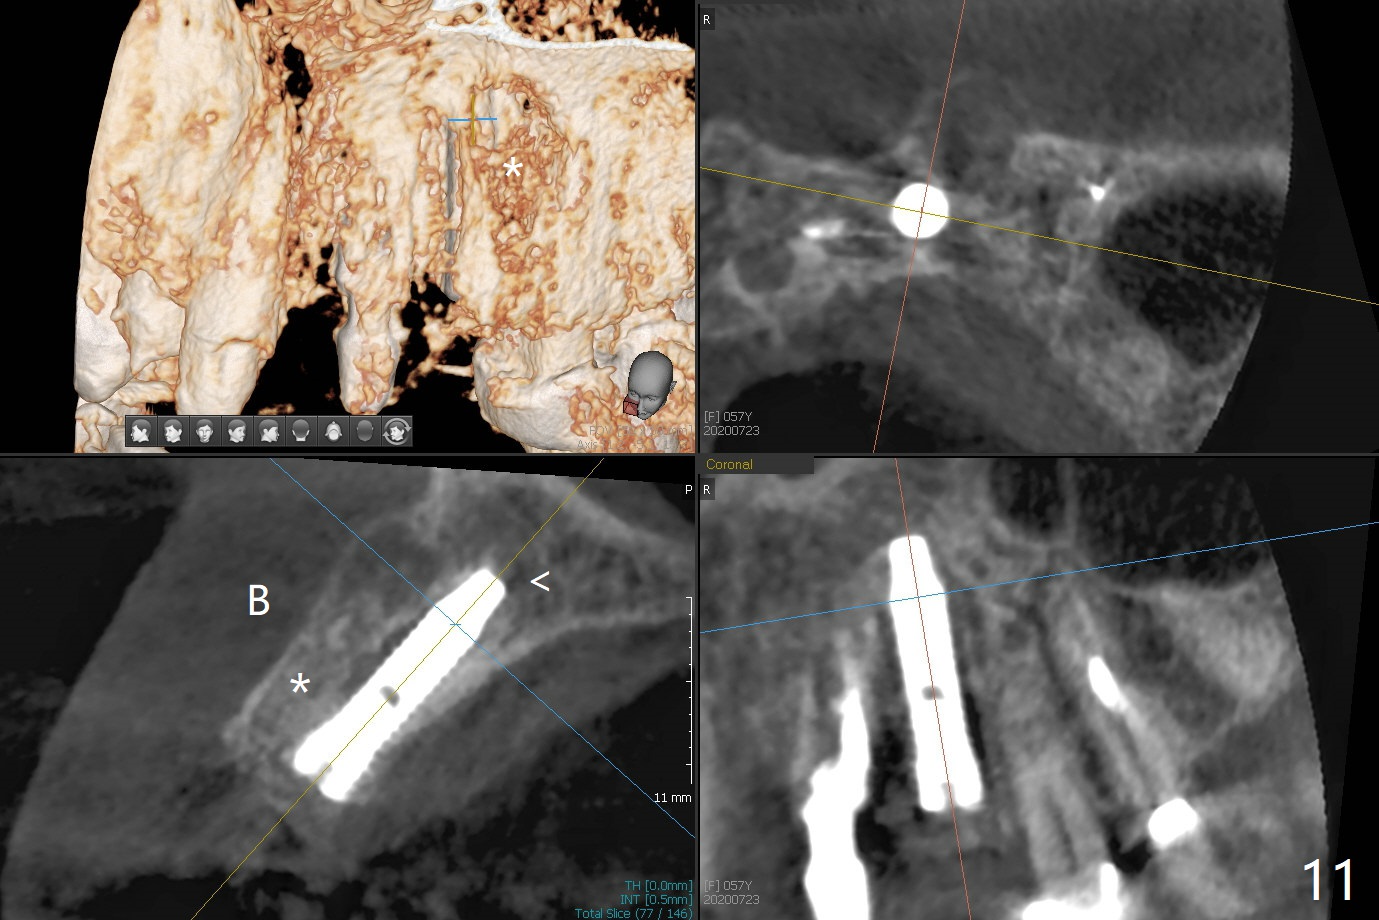

上前牙桥撤除显示右上1,2牙齿以及左上2叶片状植体好像可以保留,而左上3牙齿不能(图一,二(<:托牙边缘压迹)),拔除左上3牙齿后, 暂时把牙桥回位(图三:FPD(已经去除左上3号牙牙冠))作为3号牙种植位置参考(图四至六(G:骨粉))。其实植入前,当最后一个钻头还在原位,将PRF膜和粘性骨放置颊侧根尖(但愿骨粉能放深点),因为那里骨质很薄,好像缺损。由于植体扭力很低(大约5Ncm),放置骨粉覆盖植体(图七),为了不用缝线,涂牙周胶水(图八),放置胶原膜(图九),再涂胶水(图十)固定,最后利用右上1,2号牙(去龋,build-up后)和左上2植体制作临时牙桥,并且覆盖左上3牙槽窝。术后即刻CT显示植体颊侧(B)骨粉(图十一:*)。<:植体根尖仍有间隙,植体应该再长2毫米,初步稳定性会好些。左上3植牙愈合后,将与左上2植体制作左上1-3悬臂桥,右上1,2号牙将做根管治疗,桩,牙冠。临时牙桥术后十一天松动,右上一,二牙牙髓活性测定正常,深洗后,再次build up,不小心把左上3胶原膜吹掉,下面骨粉还稳定。术后三周病人回来做右上六种植,前牙临时修复体(图十二)需要修改(图十三)。拍摄三个方向照片显示前牙牙龈乳头(颊侧和咬合面)。

The mesiobuccal margin at #8 is redefined 4 weeks postop (Fig.14) so that the cervical end of the temporary crown is able to move mesially (Fig.13). The most coronal portion of the bone graft at #11 begins to be detached (*). The mesial portion of the abutment at #10 will be removed (curved white line) in the following week. After removing the most coronal portion of detaching bone graft at #11, acrylic is added to form a concave pontic (Fig.15 ^). With removal of the mesial portion of the abutment at #10, the retainer is moved distal (>). Pontics form at UL1 and 3 two months postop (Fig.16 *), while there is buccal atrophy at UL1,2 (Fig.17). 术后3个月植牙区牙龈形态良好(图十八),即将暴露,放置愈合基台。图十九是在右上1根管治疗时(基台放置后五天)拍摄。左上3术后3个月3个星期,1,2唇侧塌陷(图二十)。叶状植体处牙槽嵴往根尖萎缩(图二十一:^)。尽管做了松弛切口,放入事先预备的粘性骨粉后,几乎没有空间放置结缔组织移植物,恰好还没有取。放置PRF膜后,使用4-0 Monoglyc缝线缝合。牙龈似乎冠方移位(图二十二:箭头)。植骨后,唇侧仿佛饱满多了(图二十三:*)。骨粉放置于左上1,2唇侧和牙槽嵴(图二十四:*,与之前(图十九)对比)。后者有助于牙龈冠方移位,而前者有助于增加唇侧饱满度。植骨术后两周唇侧仍饱满(图二十五,六)。植骨后四个月牙冠粘固,两个月后,病人抱怨10号牙左右食物坎塞(图二十七),9/10牙冠撤除,10基台边缘加深,重做临时牙冠,同时增加9凹陷(pontic)。一个月后,9/10临时牙冠修整两次,11永久性牙冠撤除,也制备临时牙冠,外形明显改善(图二十八)。